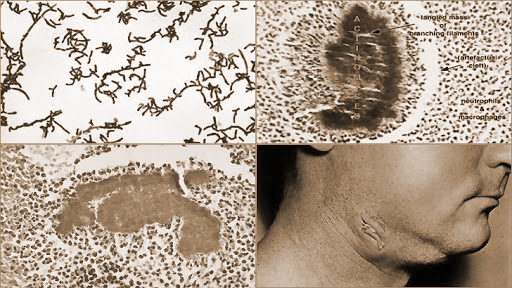

Aktinomikoz, insanlarda ve sığırlarda, Actinomyces cinsinden iki tür ışılküf bakterisinin yol açtığı bulaşıcı olmayan enfeksiyon. En çok yüz, boyun, göğüs ve karında görülen çok sayıda ağrılı, irin dolu sert şişiklerle tanımlanan hastalığın etkeni sığırlarda Actinomyces bovis, insanlarda Actinomyces Israeli dir ve sığırlarda gelişen hastalık “ışılküflüce” adıyla da bilinir.

Hastalık yapıcı organizma, özellikle oksijensiz ortamları sevdiği için insanlarda en çok ağız ve bağırsaklarda yaşar. Hastalık ölü dokuların doğrudan yayılmasıyla ortaya çıkar. Boyun, yüz ve özellikle yüzde 50 oranında görülen çene lezyonları genellikle ağızdaki bir yaradan kaynaklanır ya da diş çekiminden sonra başlar. Karın lezyonları ise apandisitten ya da mide, kalınbağırsak delinmelerinden sonra görülebilir.

Akciğerlerde ve çevresinde gelişen enfeksiyonlar, hastalık etkeninin solunum yoluna girmesinden ileri gelir ve genellikle kilo kaybı, gece terlemeleri, öksürük, yüksek ateş gibi belirtiler verir. Enfeksiyon çok ender olarak kol ve bacaklarda, beyinde ve kalp kapakçıkla-nnda da görülebilir. Bazen de kan dolaşımıyla yayılarak vücudun birçok bölgesinde lezyonlara neden olur. Antibiyotiklerle yapılan tedavi, cerahatin drenle akıtılması ya da erişilebilen lezyonlann temizlenmesi gibi cerrahi yöntemlerle desteklenebilir.